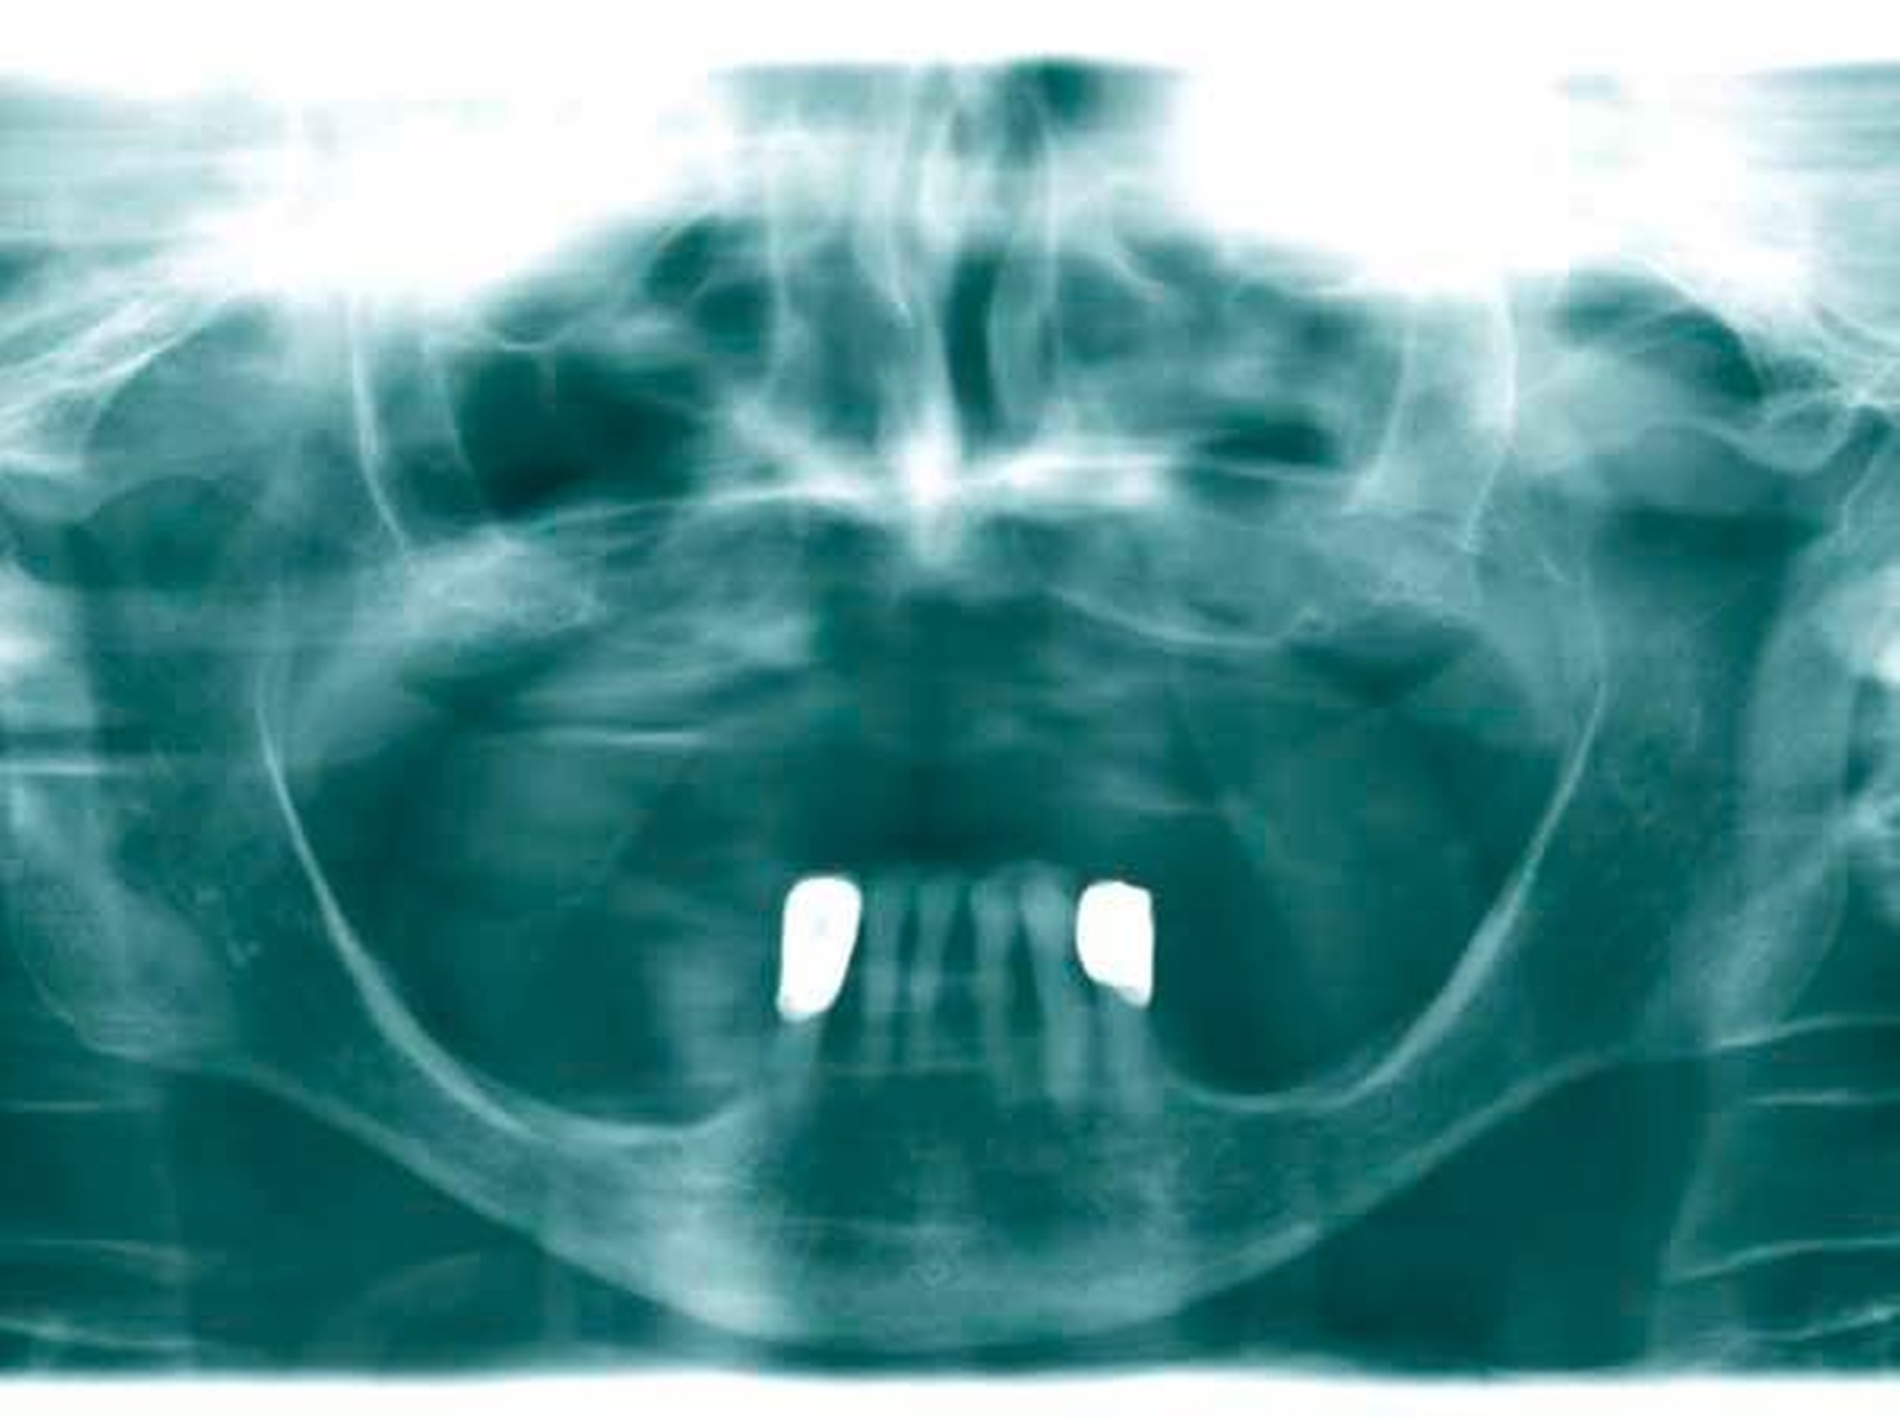

Das Orthopantomogramm (Abbildung 1) zeigt die desolate Gebisssituation einer 31-jährigen Patientin mit ansonsten unauffälliger Anamnese. Die Patientin wurde nach Abschluss der Extraktionstherapie zur prothetischen Beratung und Weiterbehandlung an unsere Poliklinik überwiesen.

Das Orthopantomogramm (Abbildung 7) zeigt die Gebisssituation eines 89-jährigen Patienten mit kardiovaskulärer Anamnese (Herzinfarkt, Stent-Implantate) und deutlich reduziertem, fast hinfälligem Allgemeinzustand. Der Patient erhält 14(!) verschiedene Medikationen. Der überweisenden Kollegin erschien die Behandlung in der Praxis zu riskant. Nach Abschluss der Extraktionstherapie stellte sich der Patient zur prothetischen Beratung und Weiterversorgung an unserer Poliklinik vor. Im Oberkiefer wurde ein totaler Zahnersatz geplant. Im Unterkiefer verblieb ein karies- und füllungsfreies Restgebiss von 33 nach 42 (Abbildung 8). Aus gesundheitlichen Gründen schied eine Präparation der karies- und füllungsfreien Zähne für die Aufnahme von Doppelkronen oder metallkeramischen Kronen mit oralen Fräsungen aus.